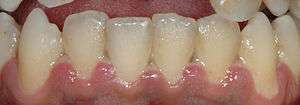

Dentin hypersensitivity is a sharp, short-lasting dental pain occurring in about 15% of the population,[15] which is triggered by cold (such as liquids or air), sweet or spicy foods, and beverages.[16] Teeth will normally have some sensation to these triggers,[17] but what separates hypersensitivity from regular tooth sensation is the intensity of the pain. Hypersensitivity is most commonly caused by a lack of insulation from the triggers in the mouth due to gingival recession (receding gums) exposing the roots of the teeth, although it can occur after scaling and root planing or dental bleaching, or as a result of erosion.[18] The pulp of the tooth remains normal and healthy in dentin hypersensitivity.[9]:510